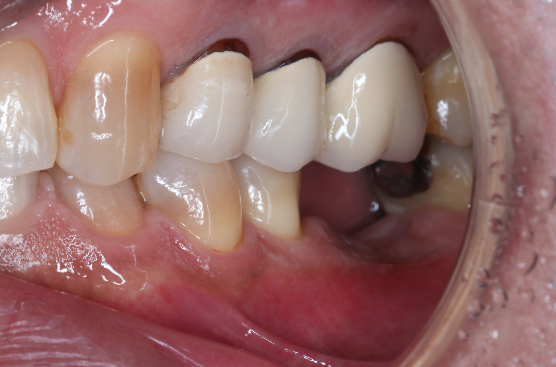

症例②

年齢50代男性

治療期間4ヶ月

治療内容セラミック治療、インプラント治療

治療箇所

インプラント:左下6番

セラミック:左上4番、5番、7番 左下7番 右下6番 右上5番

治療費用950,000円